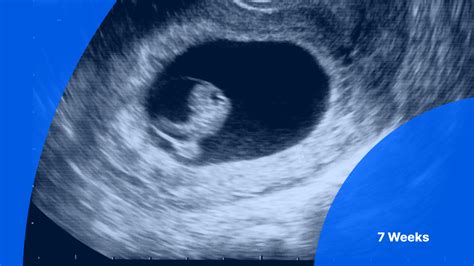

7 weeks pregnant dry lips. . ...